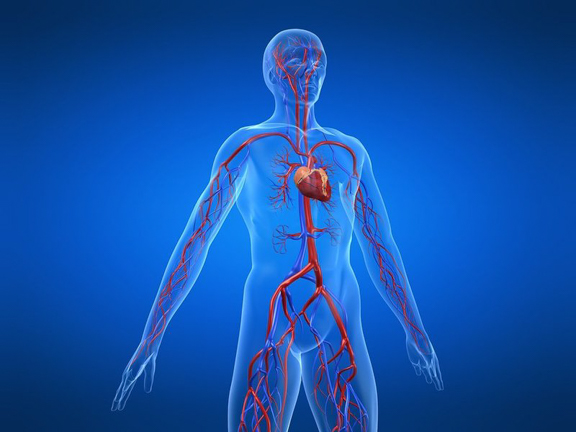

Кровеносная система

Кровеносная система – одна из основных человеческих систем.

Система кровообращения представлена :

— Сердцем;

— Кровеносными сосудами;

— Кровью.

Сердце – это, так называемый, насос, который качает кровь, в одном направлении, по кровеносной сети. Длина кровеносных сосудов в человеческом организме составляет около 150 тысяч километров, каждый из которых выполняет индивидуальную функцию.

Крупные сосуды системы кровообращения :

— Яремная вена;

— Подключичная вена;

— Аорта;

— Легочная артерия;

— Бедренная вена;

— Сонная артерия;

— Верхняя полая вена;

— Подключичная артерия;

— Легочная вена;

— Нижняя полая вена;

— Бедренная артерия.

Кровеносная система человека

Кровь – это одна из базовых жидкостей человеческого организма, благодаря которой органы и ткани получают необходимое питание и кислород, очищаются от токсинов и продуктов распада. Эта жидкость может циркулировать в строго определённом направлении благодаря системе кровообращения. В статье мы поговорим о том, как устроен этот комплекс, благодаря чему поддерживается ток крови, и каким образом система кровообращения взаимодействует с другими органами.

Сердечно-сосудистый комплекс

Система, включающая сердце и все сосуды, начиная с самых крупных и заканчивая микроскопическими капиллярами диаметром в несколько микрон, обеспечивает циркуляцию крови внутри организма, питая, насыщая кислородом, витаминами и микроэлементами и очищая от продуктов распада каждую клеточку человеческого тела. Эту гигантскую по площади сложнейшую сеть нагляднее всего демонстрирует анатомия человека в картинках и схемах, поскольку теоретически разобраться, как и куда ведёт каждый конкретный сосуд, практически нереально — их количество в организме взрослого достигает 40 млрд и более. Тем не менее, вся эта сеть является сбалансированной замкнутой системой, организованной в 2 круга кровообращения: большой и малый.

В зависимости от объёма и выполняемых функций сосуды можно классифицировать следующим образом:

«Двигателем» столь крупной замкнутой сети является сердце — полый мышечный орган, благодаря ритмичным сокращениям которого кровь продвигается по сосудистой сетке. При нормальной работе каждую минуту сердце перекачивает не менее 6 литров крови, а за день — примерно 8 тысяч литров. Неудивительно, что сердечные заболевания являются одними из самых серьёзных и распространённых, — с возрастом этот биологический насос изнашивается, поэтому необходимо тщательно отслеживать любые изменения в его работе.